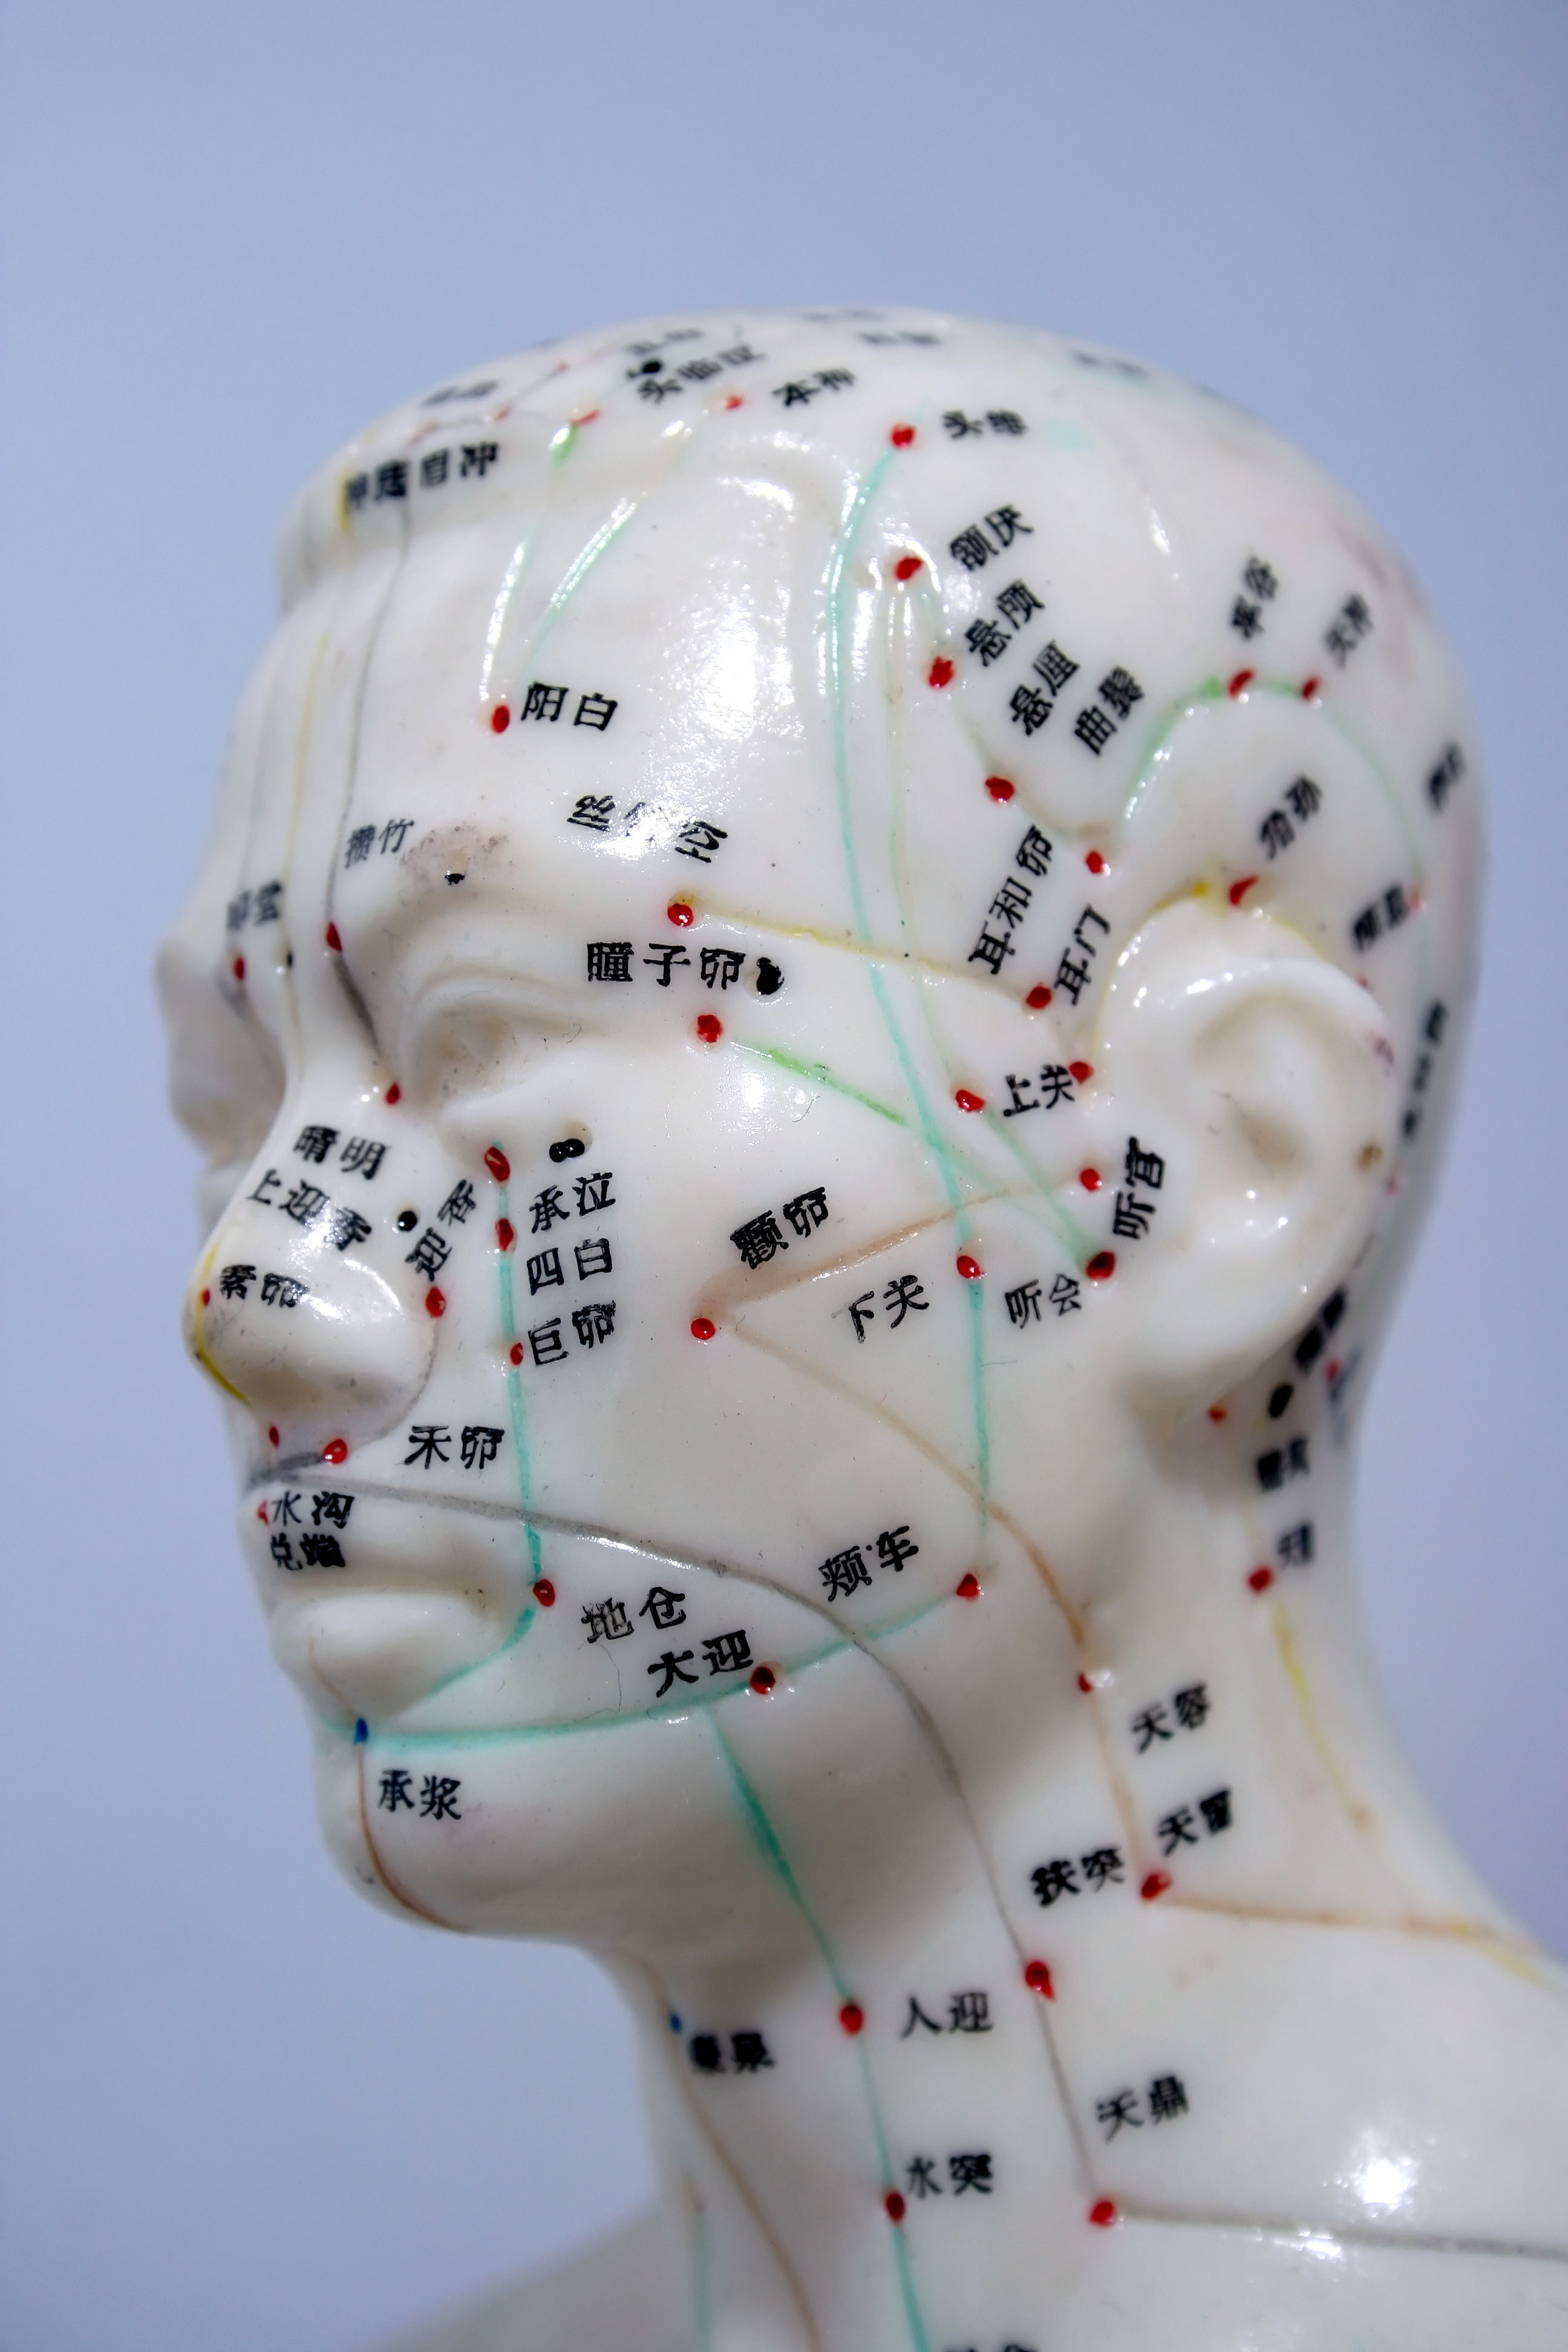

Gli aghi utilizzati nell’agopuntura aiutano ad alleviare i dolori grazie al fatto che innescano nell’organismo la produzione di una sostanza chimica, l’adenosina, di fatto un vero e proprio antidolorifico naturale.

Lo rivelano sulla rivista Nature Neuroscience i ricercatori del Center for Translational Neuromedicine presso il Medical Center dell’Università di Rochester, che inoltre suggeriscono come l’agopuntura potrebbe essere doppiamente efficace se associata ad una terapia a base di deossicoformicina, un farmaco antitumorale che sembra avere la capacità di mantenere alti i livelli di adenosina nell’area trattata.

Lo rivelano sulla rivista Nature Neuroscience i ricercatori del Center for Translational Neuromedicine presso il Medical Center dell’Università di Rochester, che inoltre suggeriscono come l’agopuntura potrebbe essere doppiamente efficace se associata ad una terapia a base di deossicoformicina, un farmaco antitumorale che sembra avere la capacità di mantenere alti i livelli di adenosina nell’area trattata.